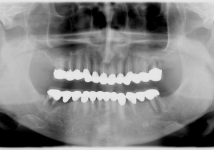

正面

レントゲン写真

<症例3>30歳代 女性

歯科治療への恐怖心から長い間放置されていた患者様が、口腔内の清掃状態悪くなり、腫れや痛みが出て当院を受診され、除菌とブラッシング指導を受け、歯石除去をすることにより、歯肉の炎症が治まり、全顎的に治療を行いました。仮歯で患者様の満足度を確認し、審美改善して最終仕上げをしました。